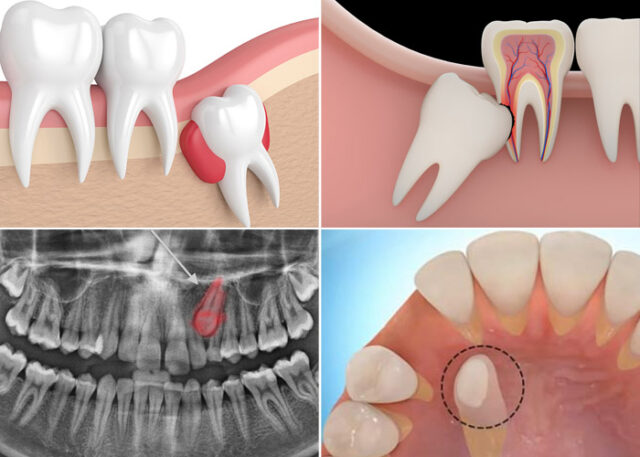

Răng số 3 mọc ngầm không chỉ đơn thuần là nằm ẩn mình, nó còn gây ra nhiều tác động gián tiếp lên các răng lân cận:

- Tạo khoảng hở trên cung hàm: Răng số 3 không xuống có thể làm răng lân cận (răng cửa bên, răng tiền hàm) dịch chuyển, tạo khoảng hở lớn và mất thẩm mỹ.

- Tiêu chân răng cửa bên: Nếu răng số 3 mọc ngầm nghiêng và áp sát chân răng số 2, áp lực lâu ngày có thể gây tiêu chân răng, làm răng cửa yếu, lung lay hoặc phải nhổ.

- Sai khớp cắn và đau khớp thái dương hàm: Thiếu răng số 3 làm mất chức năng dẫn hướng khớp cắn, khiến răng hàm chịu lực nhai lớn hơn, dẫn đến sai khớp cắn thứ phát và có thể gây đau khớp thái dương hàm (TMJ).

- Hình thành nang/u: Răng số 3 mọc ngầm có nguy cơ tạo nang hoặc u, gây tiêu xương và cần phát hiện sớm.

1. Kéo răng bằng chỉnh nha (Phương án bảo tồn)

Phù hợp với: Hầu hết các ca răng số 3 mọc ngầm, đặc biệt là ở bệnh nhân trẻ tuổi (dưới 18 tuổi) khi xương hàm còn mềm, khả năng di chuyển răng tốt.

Quy trình:

- Giai đoạn chỉnh nha tạo khoảng: gắn mắc cài toàn hàm và di chuyển răng lân cận để tạo khoảng cho răng số 3.

- Tiểu phẫu bộc lộ: tiểu phẫu nhẹ để tiếp cận thân răng số 3 mọc ngầm, gắn mắc cài và chuỗi kéo (power chain) lên răng.

- Giai đoạn kéo răng: chuỗi kéo nối vào dây cung, bác sĩ điều chỉnh lực từ từ theo lộ trình (thường 6–12 tháng) để đưa răng số 3 xuống.

- Hoàn thiện: răng số 3 về vị trí, tích hợp vào cung hàm, khôi phục thẩm mỹ và chức năng khớp cắn.